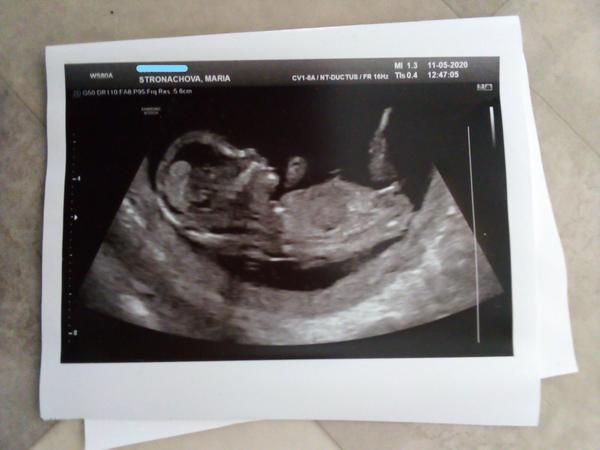

Je to holčička nebo chlapeček? Foto ultrazvuku

Ahoj maminky a budoucí maminky 😉 Prosím, poradila byste mi některá, co vidíte na fotce z ultrazvuku ve 20. týdnu za pohlaví? Určitě jste foteček viděly už mraky, proto vás žádám o radu...Nechci nikoho ovlivnit, proto svůj tip řeknu později 🙂 Děkuju moc!!!